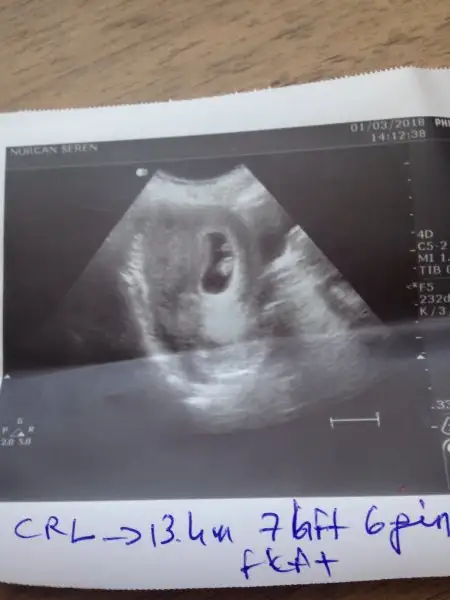

Kanama değil de kahverengi lekelenme ..bugün 7+6 olduğumu söyledi doktor boyutu da 13.4 mm imişKaçıncı ayda böyle kanama oldu sizin?